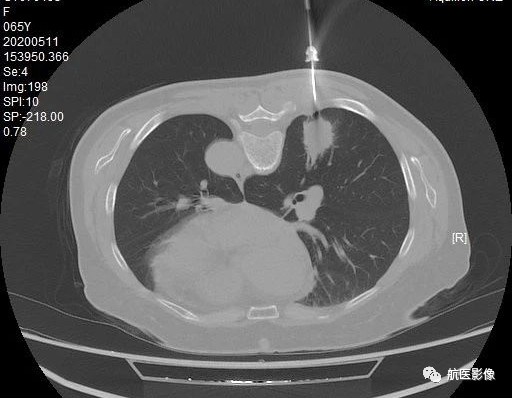

10. CT引导下肺活检:

利用CT定位引导肺穿刺抽吸或切针活检获取病理组织是一种微创、安全、准确的检查方法。 对于临床肺部病变的定性诊断、治疗方案的制定和预后的评估非常有用。 价值。